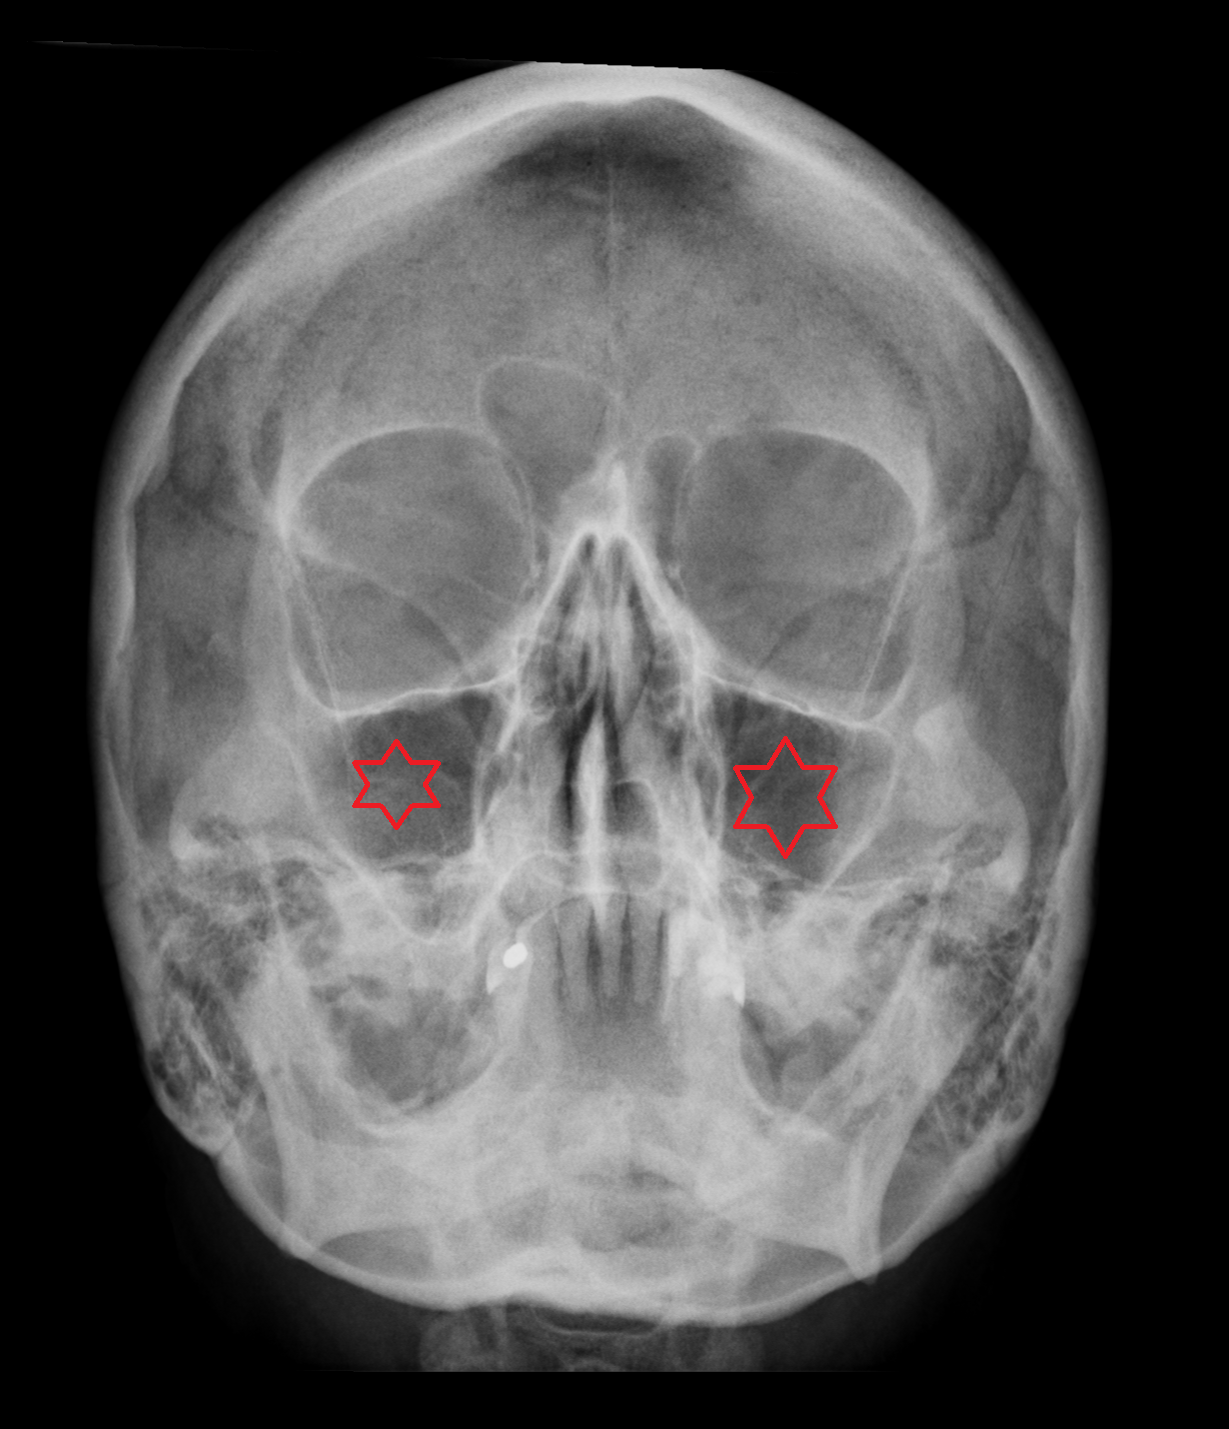

- Maxillary sinus

- Middle nasal concha

- Inferior nasal concha

- Orbital plate